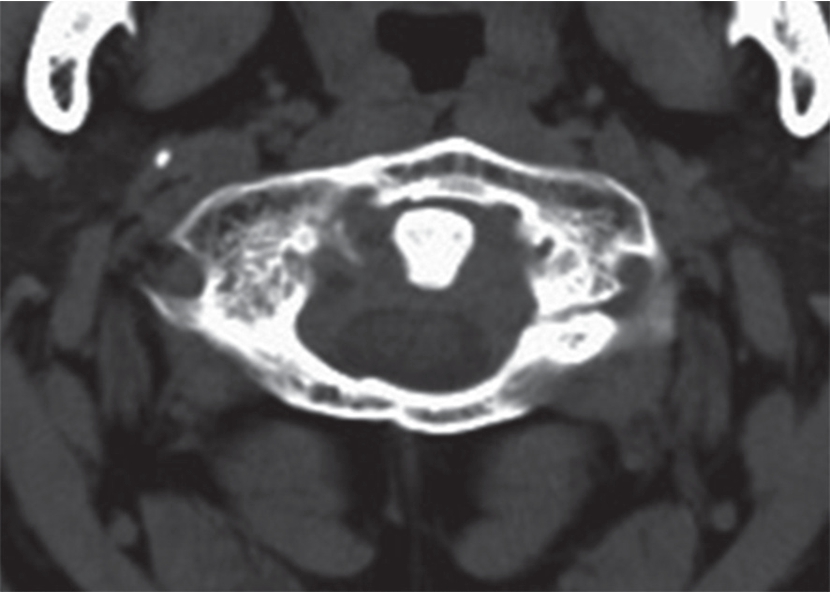

1)寰椎CT平扫:寰椎横断面可显示寰椎前结节、前弓、侧块、横突、后弓、横突孔,枢椎齿状突,茎突(图7-2-5A)。

2)下颈椎CT平扫:经椎体中部平面横断面可显示椎体、椎弓根、椎板组成的骨性椎管,椎管内可见硬脊膜囊、脊髓、硬脊膜外腔、椎体后缘的后纵韧带、附着于椎弓板内侧的黄韧带、横突及横突孔、棘突等结构。经颈椎椎间盘平面可显示椎动脉、上下关节突、椎间关节、椎板、脊髓、钩突、钩椎关节(图7-2-5B、C)。

图7-2-5 颈椎CT平扫